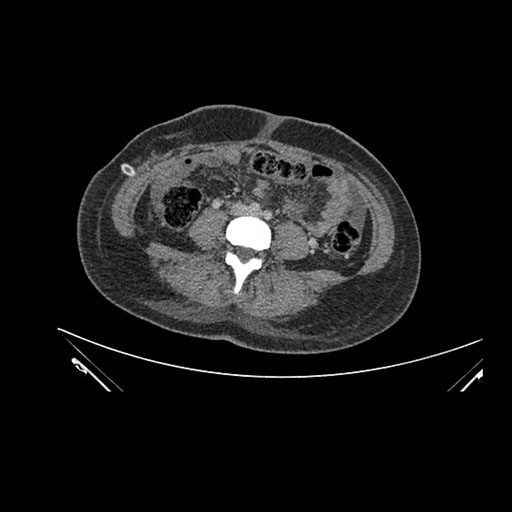

Imaging Analysis

Look through the patient's CT scan to identify any areas of concern for the necessary procedure.

Axial Arterial

Axial Venous